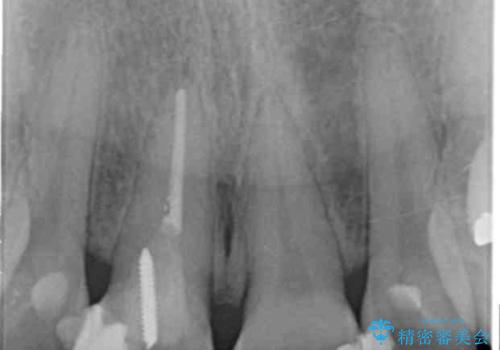

神経の治療をした歯について

神経をとる治療を行った歯は、時間が経過すると術前のように変色し見た目を大きく損ないます。

このような場合金属を使わないジルコニアクラウンを用いた治療を行うことで天然の歯のように審美性を改善することが可能になります。